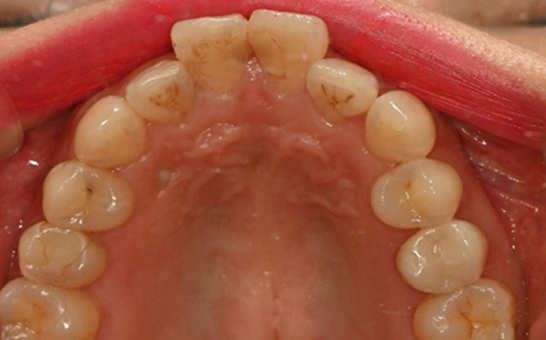

디지털 기반의 시뮬레이션 진단 과정을 통해 치아의 배열, 턱 관절 상태,

교합 상태를 정밀히 분석 후 교정 치료 계획을 수립하여 복잡한 케이스,

어려운 고난도 케이스도 전문적인 교정 치료가 가능합니다.

단순히 치아 배열만 보는 것이 아니라, 교합 상태, 치아 마모,

교정 필요성까지 정밀 분석이 가능합니다.

치아와 교합 상태를 정밀하게 분석하여

환자에게 맞는 인비절라인 치료 설계가 가능합니다.